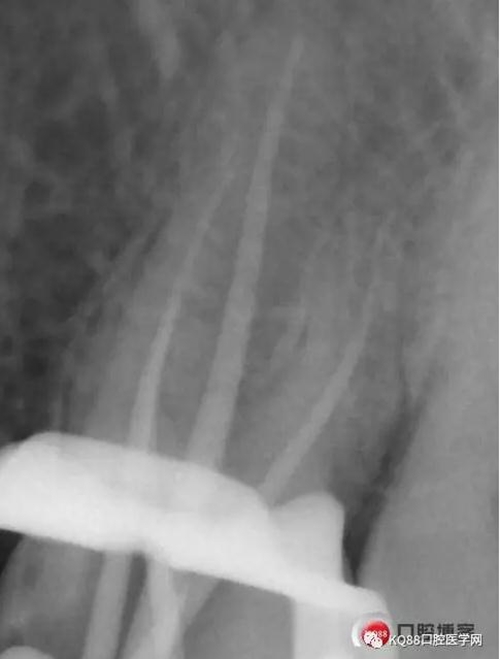

當(dāng)我第一次完成操作后,再次拍了一個(gè)插針片,發(fā)現(xiàn),距離根尖孔有1.5mm,書(shū)上說(shuō)的是2mm安全區(qū),可能如果隨意點(diǎn),就直接充填了,我想說(shuō)明的是,我們做根管,千萬(wàn)不要馬虎,不要湊合,一定嚴(yán)謹(jǐn)?shù)膽B(tài)度,于是我重新再回到C銼,再開(kāi)始耐心的預(yù)備,完成之后,再拍攝了插針片。

此次明顯可以看見(jiàn)根尖分開(kāi)了兩個(gè)根尖孔,根管治療永遠(yuǎn)就只是那一點(diǎn),如果都只是隨便做一下,我相信,沒(méi)有復(fù)雜的牙齒,根管治療都會(huì)很簡(jiǎn)單,態(tài)度決定一切,我不敢說(shuō)我做的會(huì)很好,但是我會(huì)靜下心來(lái),慢慢操作,這樣才能做得對(duì)的起自己和患者。于是根充完成,再次拍攝。